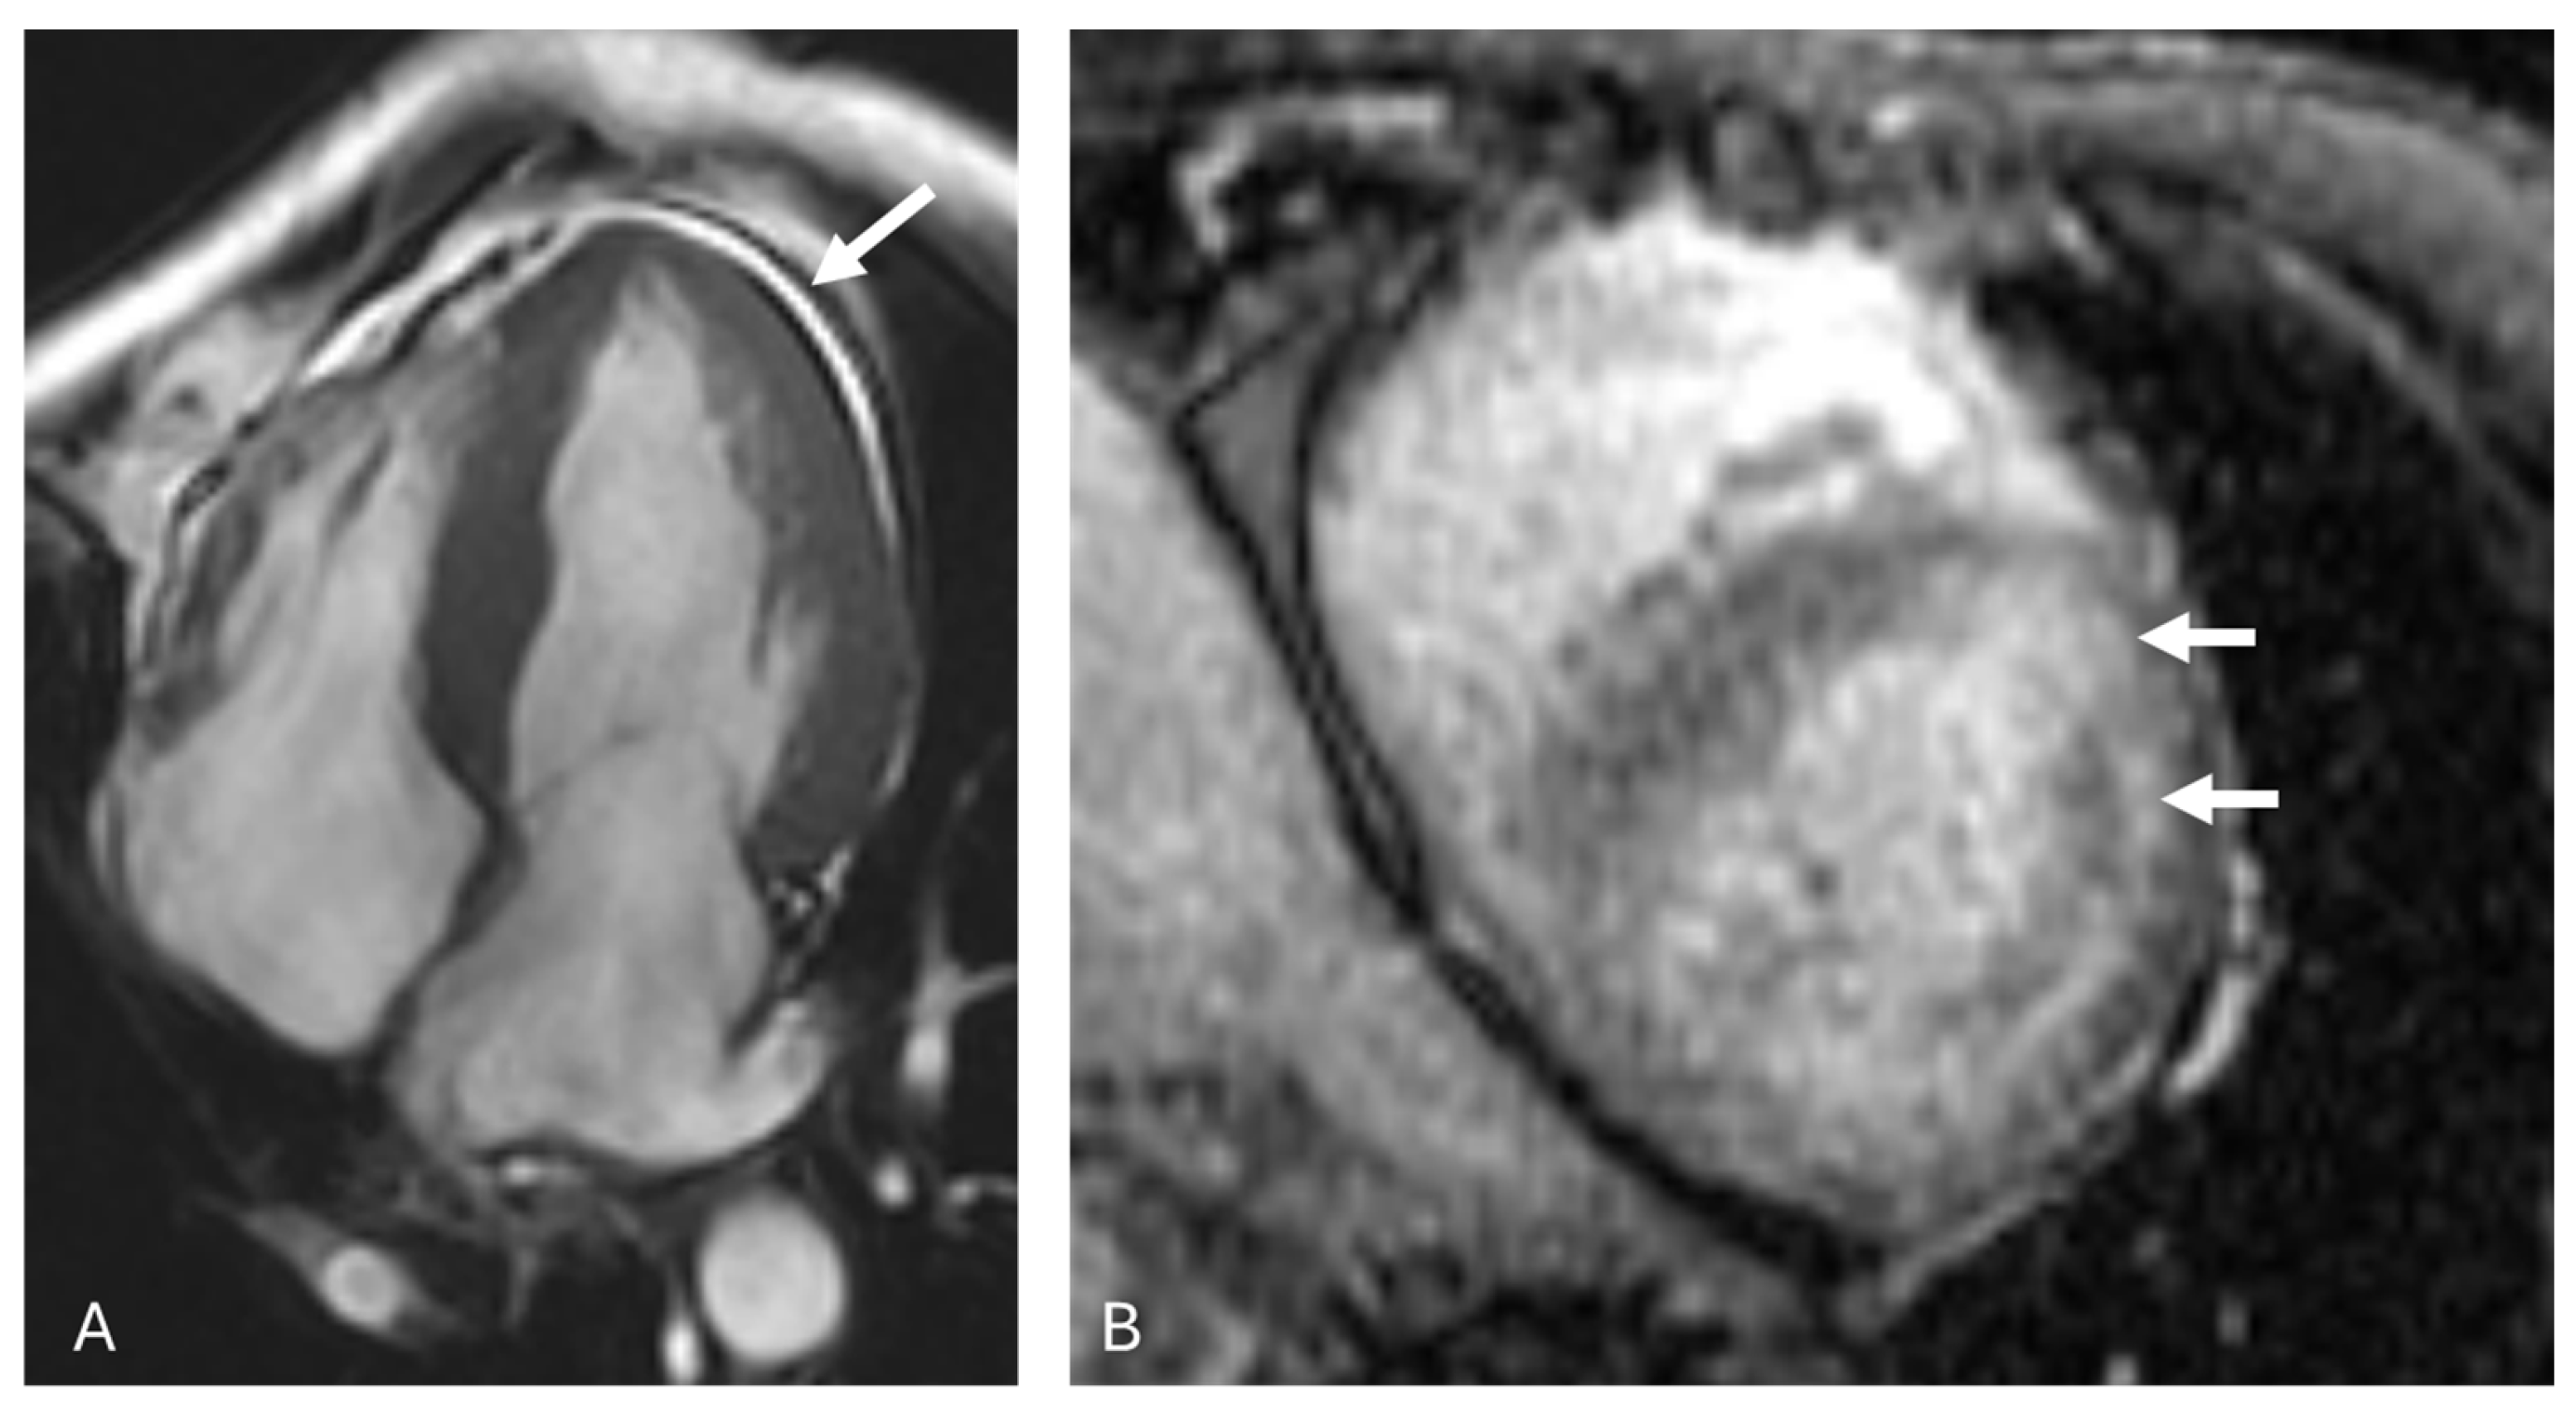

3.2. AL Amyloidosis

6. Imaging Considerations